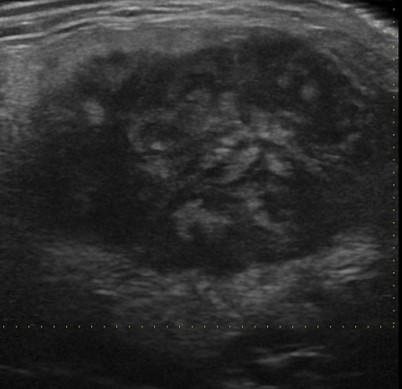

U tuyến nước bọt

U tuyến nước bọt - Ảnh 4

» Thông tin: Nam giới – 83 tuổi.

» Lâm sàng: Khối vùng mang tai.

# Ung thư biểu mô tuyến (Adenocarcinoma).